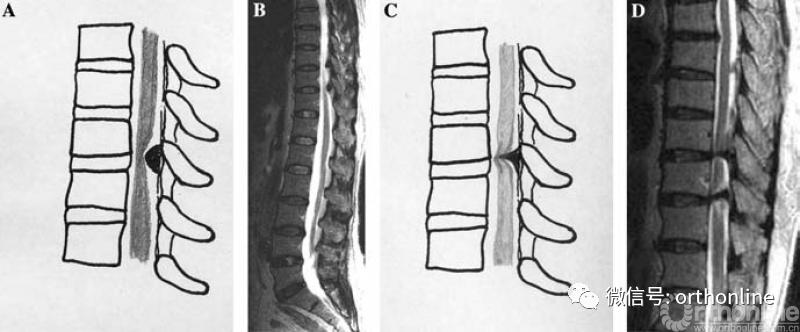

2.MRI分型:按照矢状位MRI分为圆弧形、鸟嘴型。

A.B.圆弧形(Round type);C.D.鸟嘴型(Beak type)

1.按照矢状位CT分为线型、鸟嘴型、连续波形、连续圆柱形和混合型。

OPLL的CT矢状位分型为A.线性(Linear type);B.鸟嘴型(Beak type);C.连续波形(Continuous waveform type);D.连续圆柱形(Continuous cylindrical type)。混合型(Mixed type)为同时具有A-D两种及以上类型